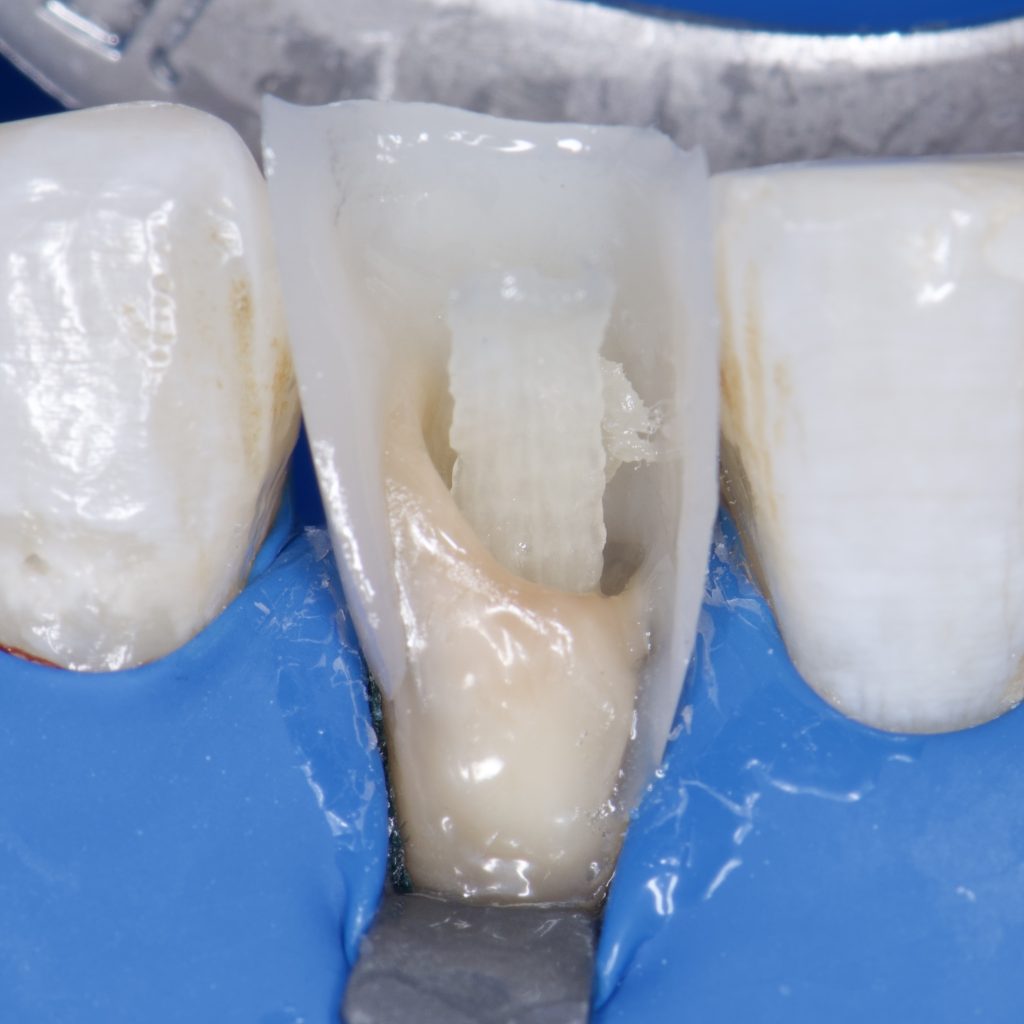

-Isolation with rubber dam

-Endodontic treatment with Bioceramic sealer and single cone

– SE clearfil bond

– Ribbond